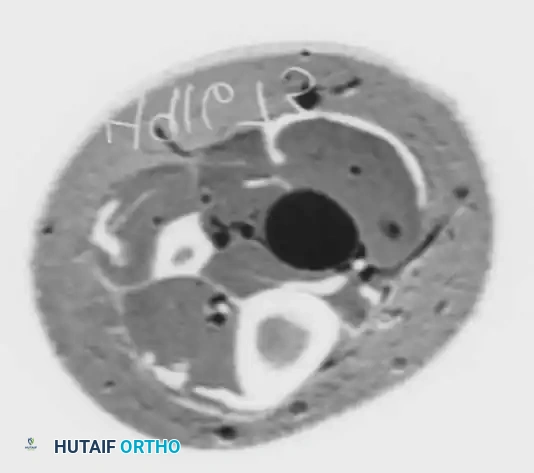

Advanced Imaging

Fig 1: Axial CT scan demonstrating a well-circumscribed soft tissue mass (neurilemoma) in the posterior medial ankle.

Fig 2: Corresponding MRI clearly identifying the neurilemoma in a 40-year-old man presenting with a positive Tinel sign. Note the distinct fullness and displacement of posterior soft tissues.

Frey and Kerr demonstrated that while MRI may not always pinpoint the exact etiology of idiopathic TTS, it is invaluable for surgical planning. MRI is the gold standard for identifying space-occupying lesions, ensuring that all areas of impingement are addressed during surgical release.